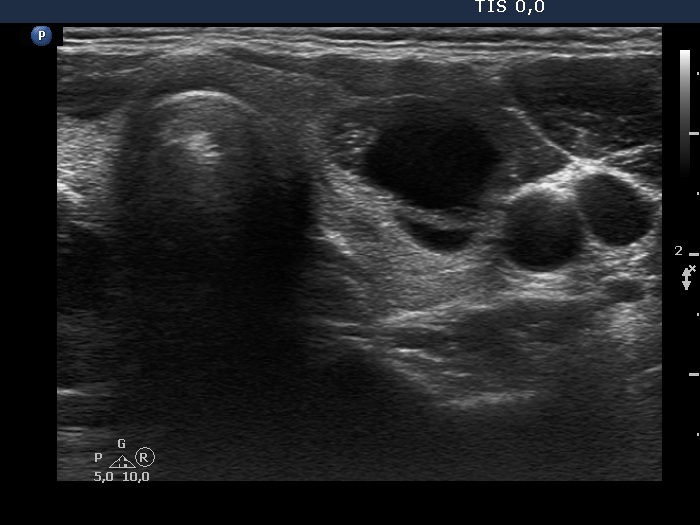

Benign cystic-colloid goiter (cytological diagnosis)

The hyperechogenic granules within the ventral solid part might be microcalcifications. The echogenic figures in the solid area cannot be the consequence of posterior enhancement because they are in front of the cystic area. Note that the nodule has in fact a moderately hypoechogenic solid part which seems to be echonormal dorsal to the cystic fluid because of the acoustic enhancement dorsal to the fluid.